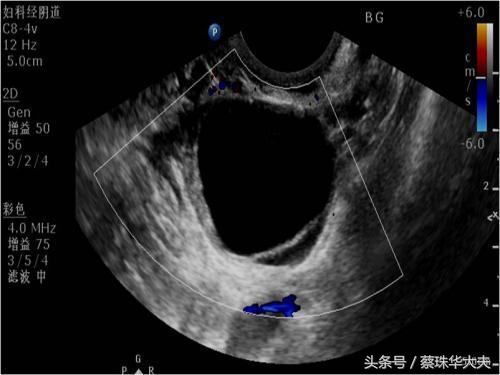

月经正常卵泡发育,所起在排卵前,月经周期28-30天的女性,在月经周期10-14天B超可看见卵泡,影像学看上去就是一个囊肿,这个囊肿大小不等,可以波动在1-3cm,如果当个月有促排卵,那这时候卵巢内卵泡更多,更大。

卵泡囊肿的特点是囊液澄清,囊壁非常光滑。所以很多女性体检是发现卵巢囊肿,一般都建议月经周期第五天或月经干净了马上复查。

所以怀孕的初期做B超时经常会发现卵巢有囊肿,如果囊肿在5cm以内,医生一般首先考虑妊娠黄体囊肿。这时候卵巢囊肿属于正常的囊肿,到怀孕70天左右,黄体功能慢慢被胎盘取代的时候,妊娠黄体囊肿完成了自己的使命,慢慢的萎缩,消失。